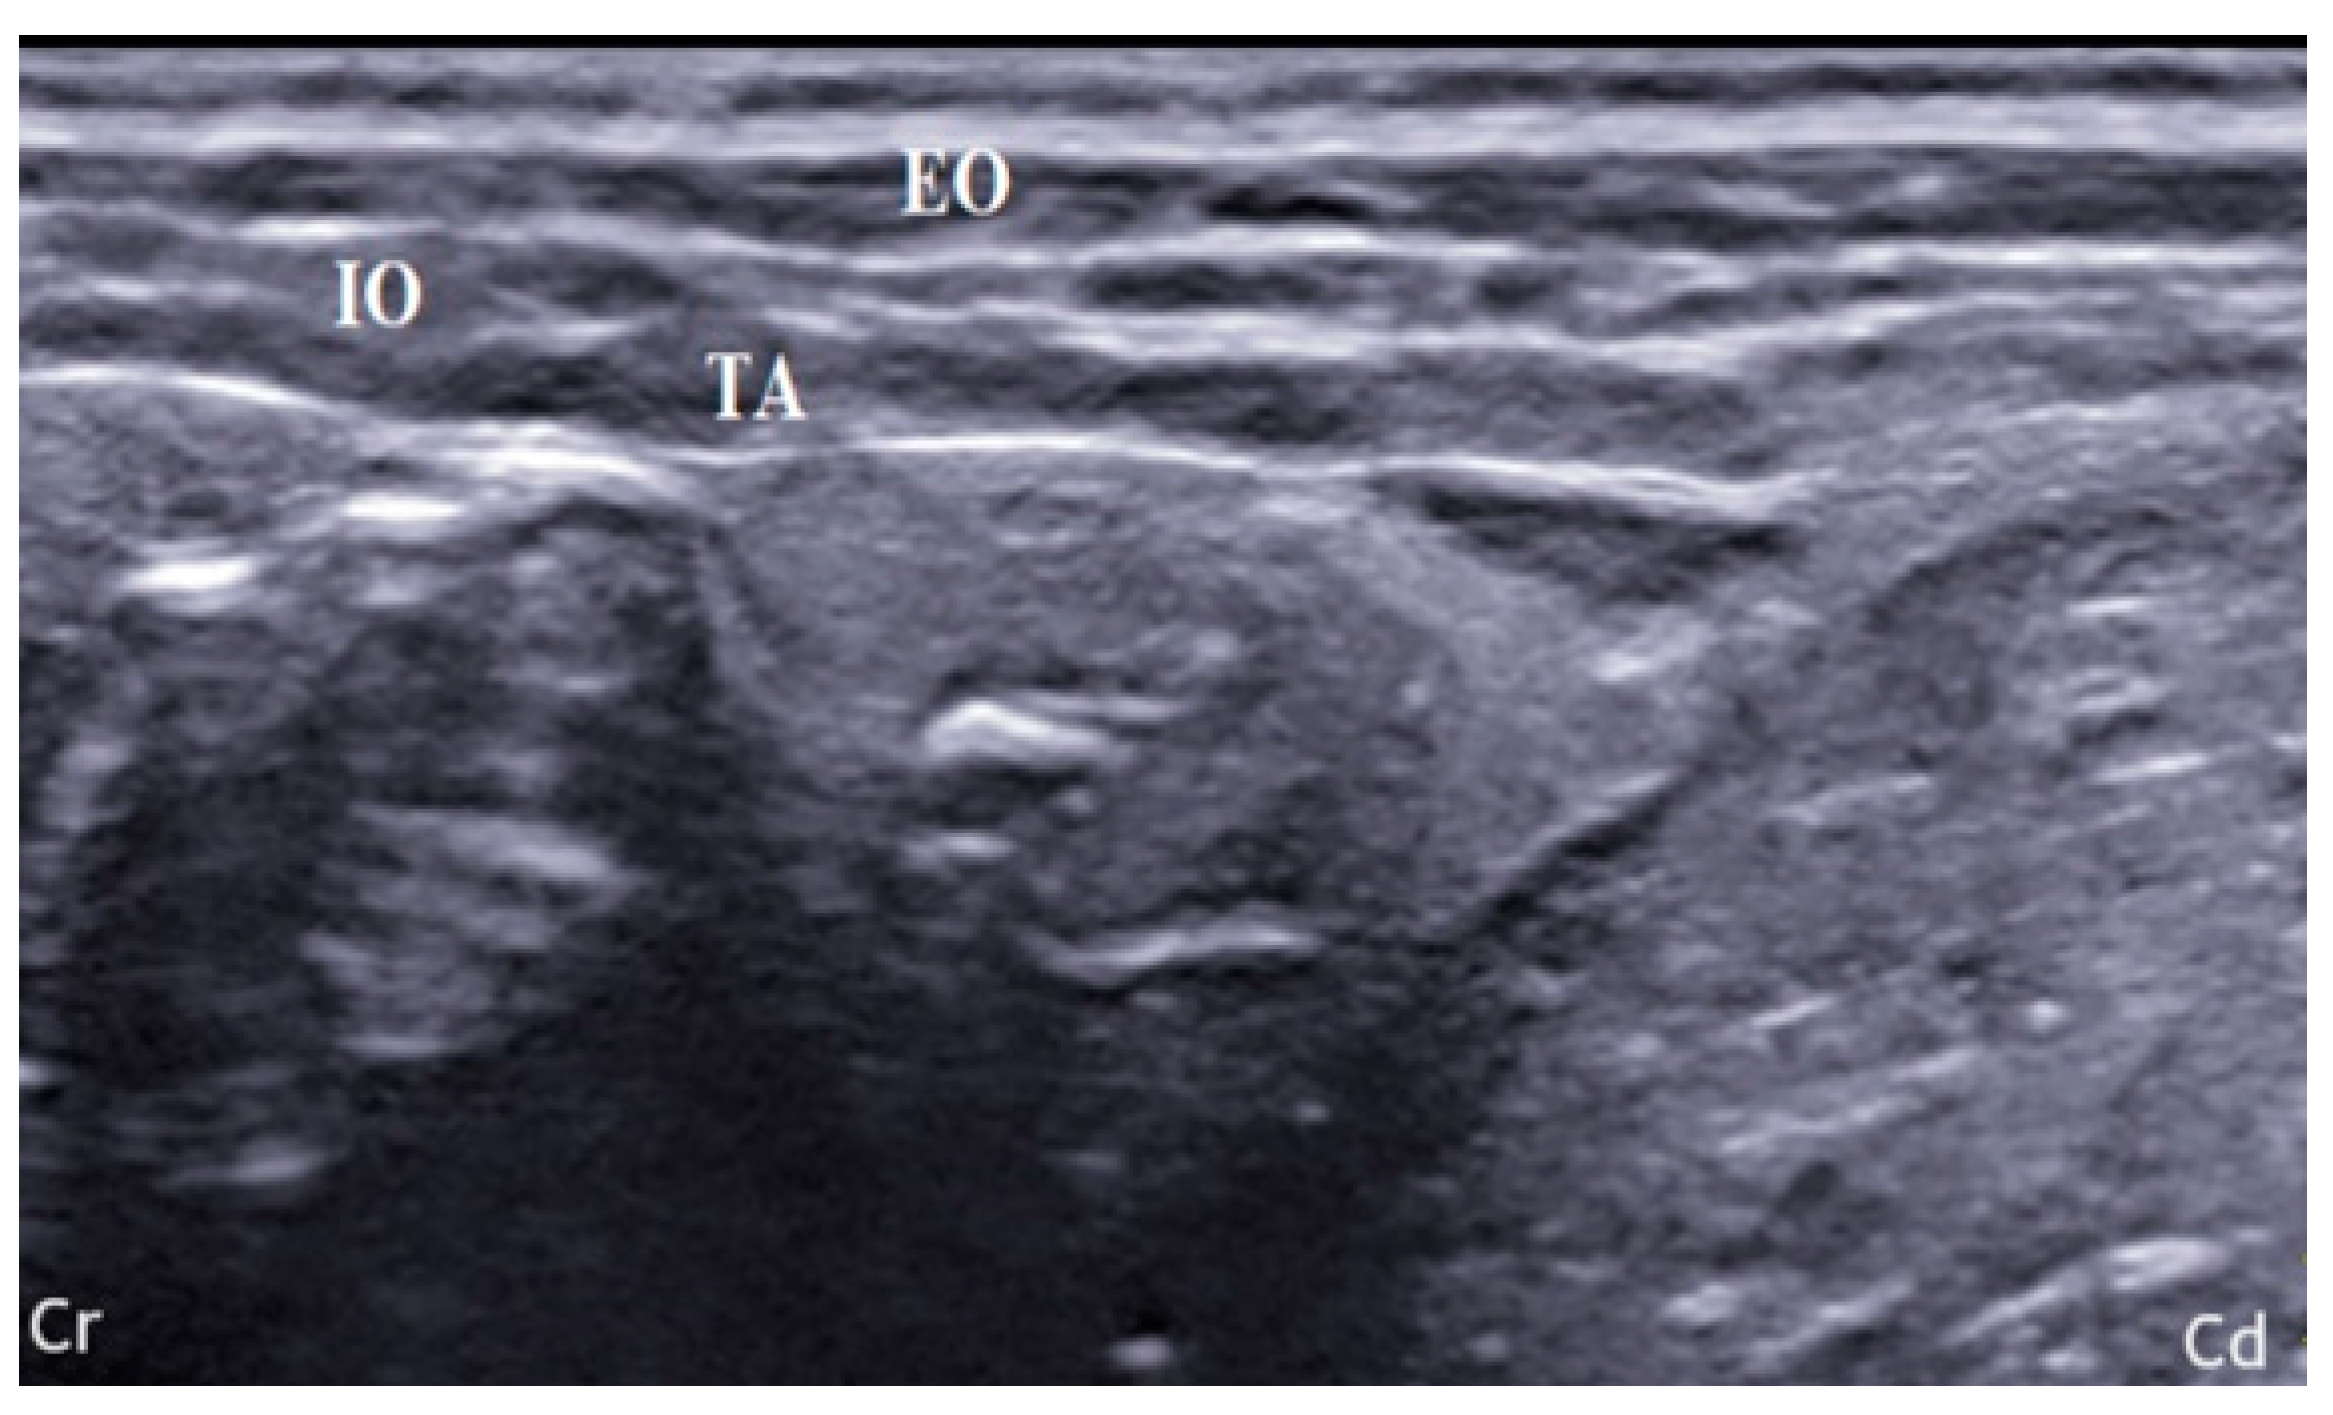

2.1. US-Guided TAP Injection

3.1. US-Guided TAP Injection